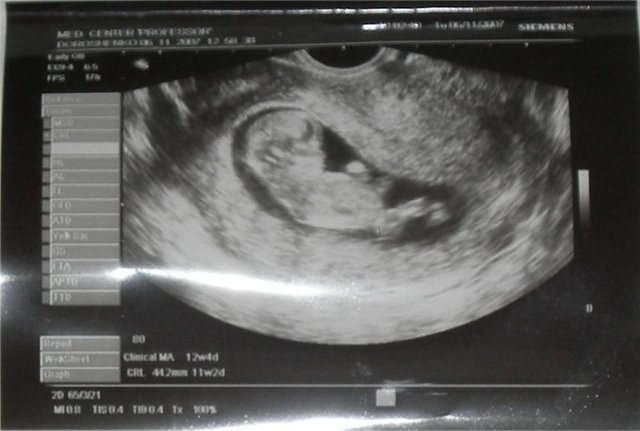

Эмбрион в первый триместр

К 30-му дню формируется общий план тела, закладываются основные органы и системы. Несмотря на внешнее сходство эмбрионов разных видов на ранних стадиях, человеческое развитие следует строго определенной последовательности.

Через восемь недель эмбрион официально считается плодом — этап, на котором он уже имеет человеческие очертания. Плацента постепенно становится полноценной системой жизнеобеспечения.